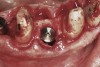

Apparently with time, stable implants placed with low initial torque develop bone characteristics around them that are similar to sites where implants were placed with a high initial torque (Figure 4 and Figure 5). Conversely, for implants placed with a high initial torque, the healing process, despite the high initial torque, provides a level of biologic stability that is not necessarily influenced by the initial insertion torque value.